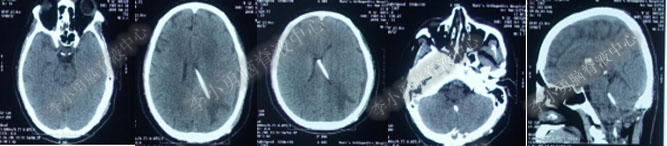

第4次出院后11天即2018年4月15日(分流术后284天,第2次的软性内镜术后179天),因引流管堵塞第5次住入该院,引流管内白色絮状物增多,引流管被堵塞。入院当天复查头部CT(图-10)显示脑室系统仍扩张。

图-10:2018年4月15日头部CT

第5次入院第2天即2018年4月17日,脑室腹壁外引流管堵塞,意识恶化,复查头部CT(图-11)示全脑室系统又较前扩大。当天急诊行左侧脑室穿刺外引流术。脑脊液化验外观黄色浑浊,并且送培养,结果是无菌生长。

图-11:2018年4月17日头部CT脑室扩张又加重

第5次入院第3天即2018年4月18日术后复查头部CT(图-12)显示脑室系统扩张较前好转。

图-12:2018年4月18日头部CT